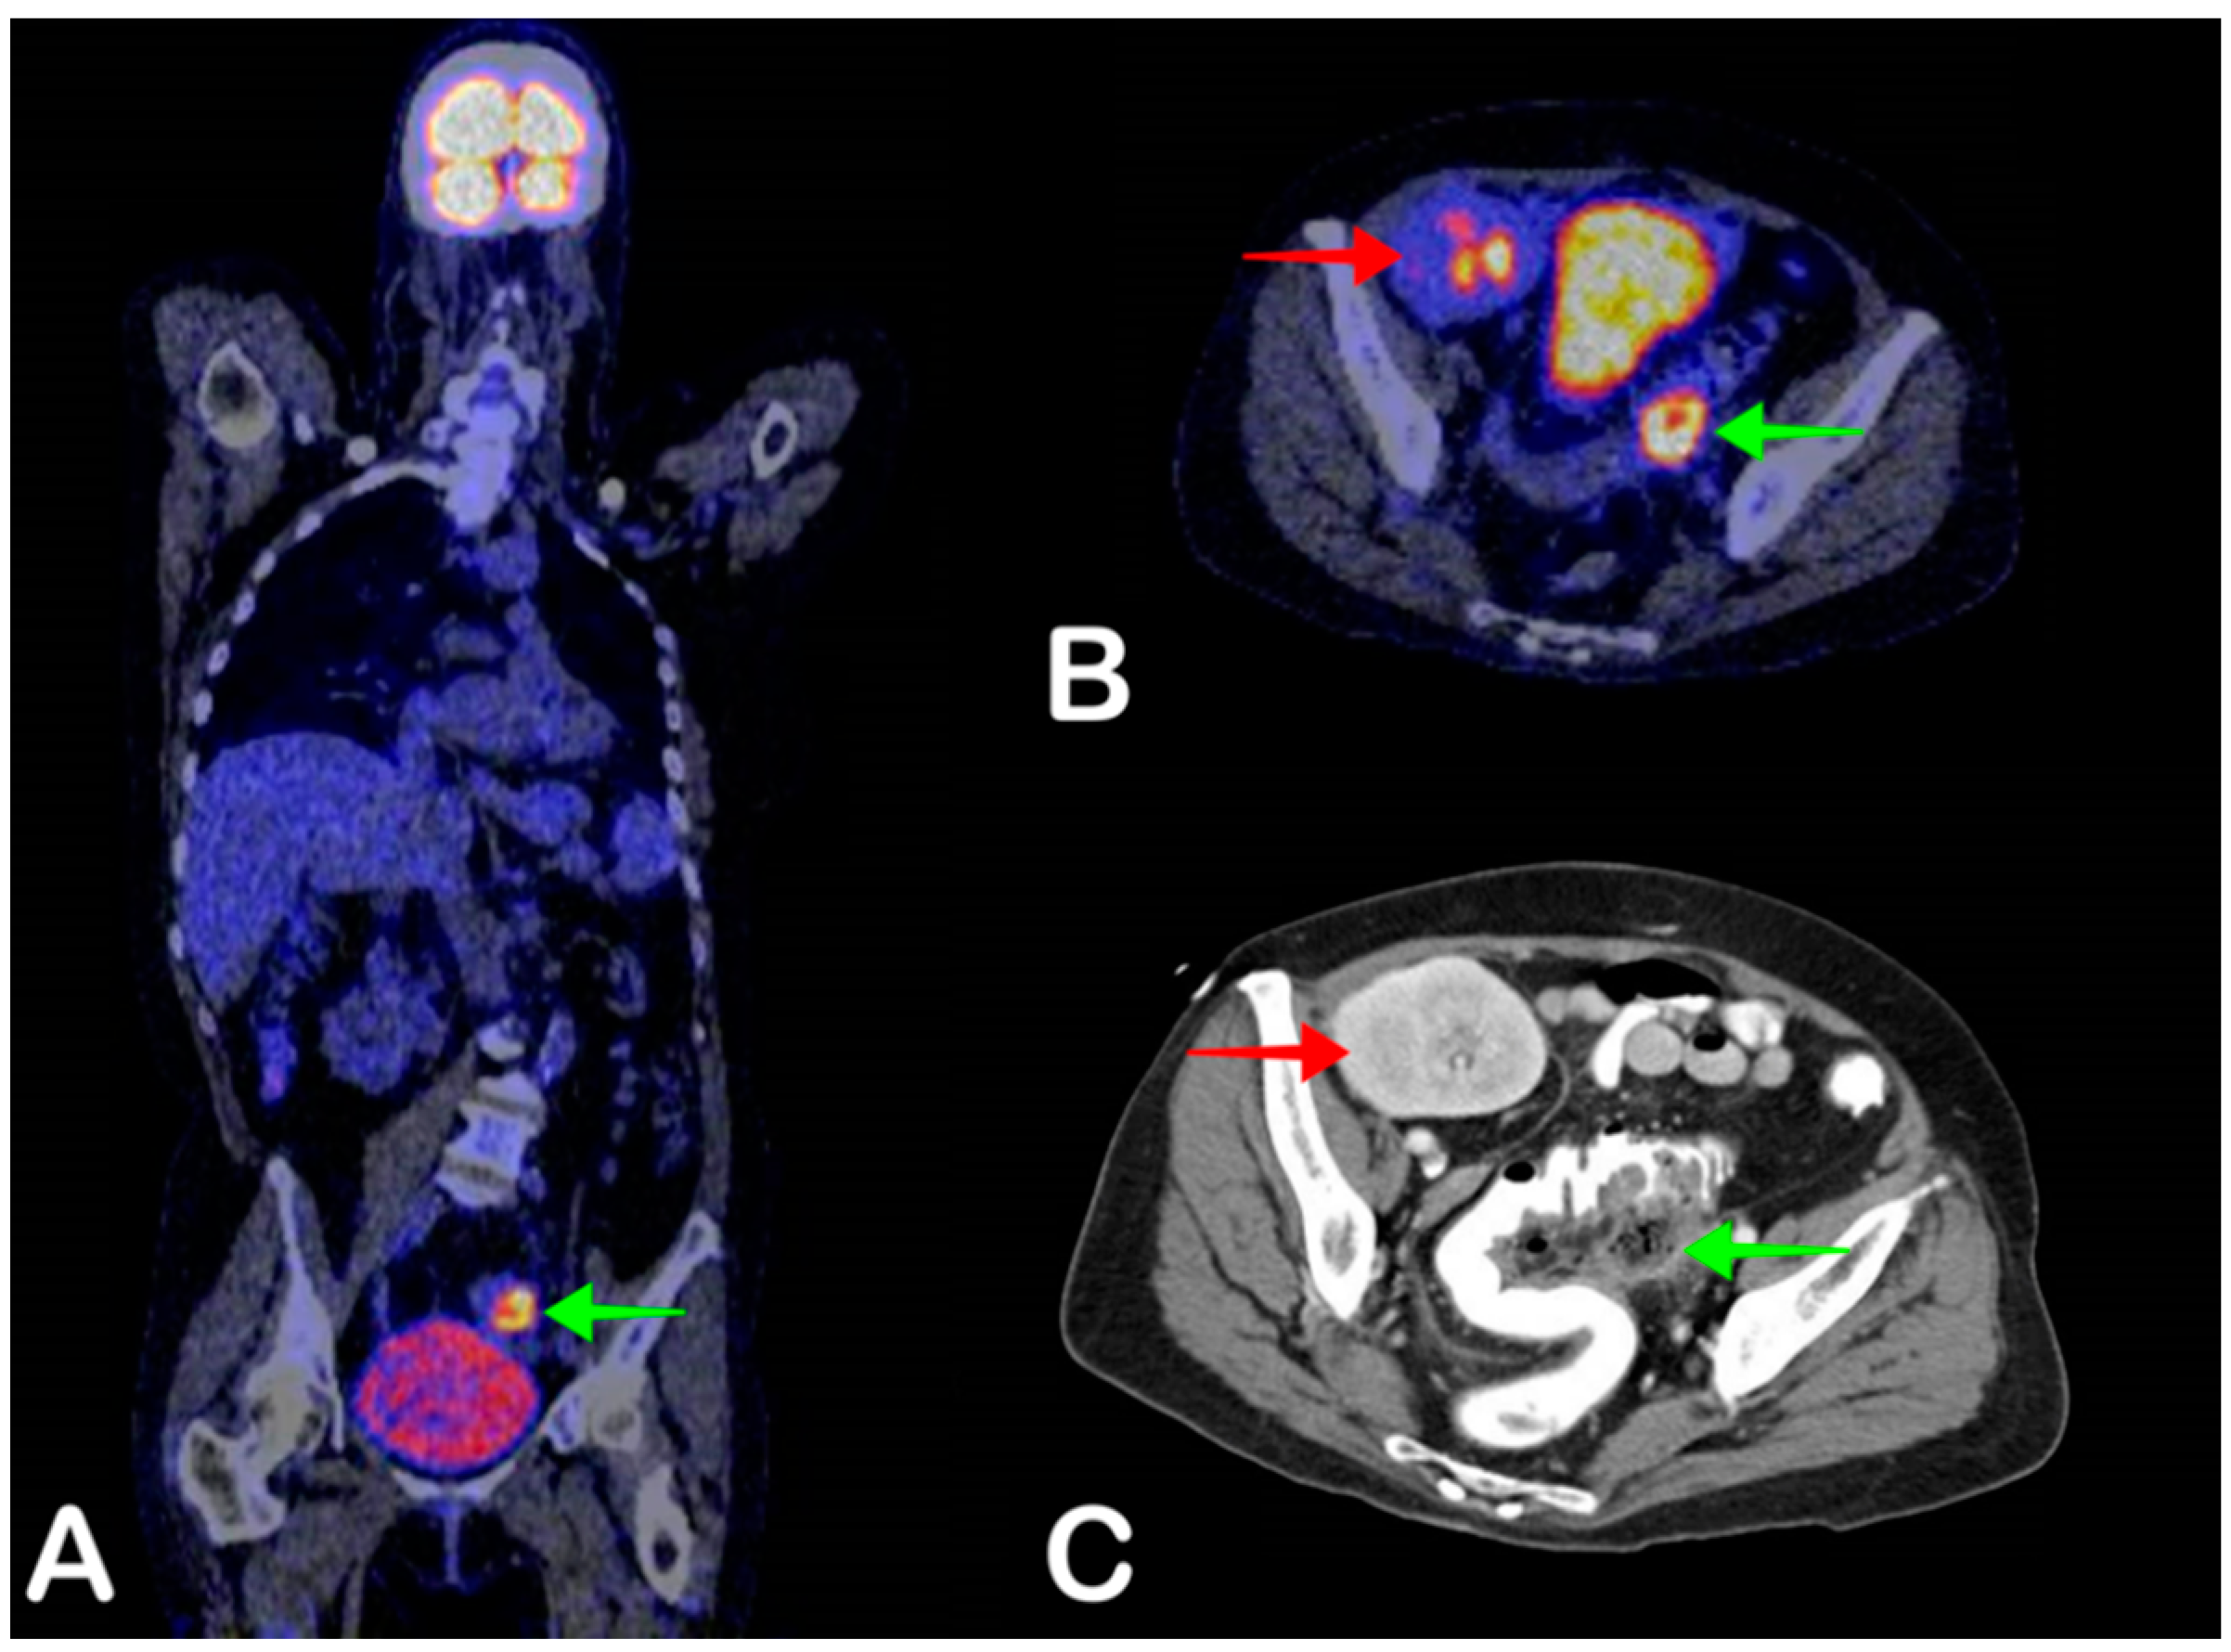

2.6. Cyst Infection

- Pijl, J.P.; Glaudemans, A.W.; Slart, R.H.; Kwee, T.C. 18F-FDG PET/CT in Autosomal Dominant Polycystic Kidney Disease Patients with Suspected Cyst Infection. J. Nucl. Med. 2018, 59, 1734–1741. [Google Scholar] [CrossRef]